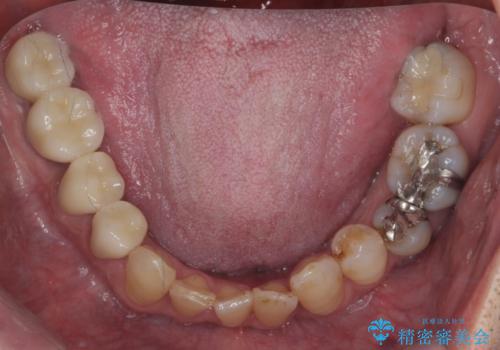

前歯の部分矯正を行い受け口を改善しました。

奥歯まで動かそうとすると顎の手術の適応になってしまうため、奥歯はそのままにして前歯のかみ合わせを改善しました。

また、奥歯はインプラント治療を行い、矯正で下の前歯を後ろに下げるのに使用しています。

時間はかかりましたがしっかり治療することができました。